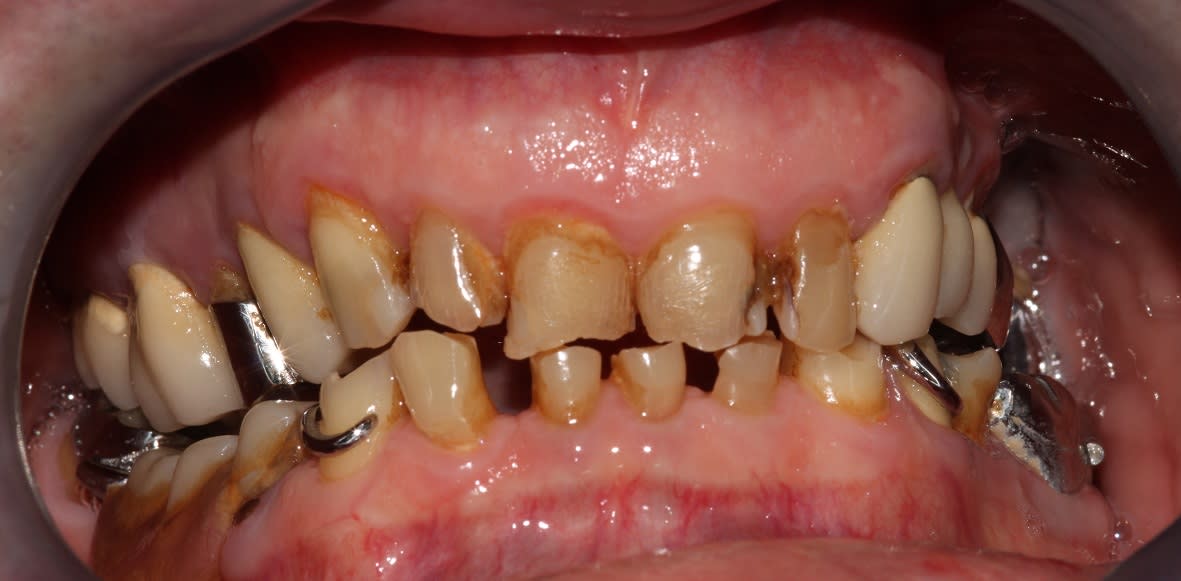

pour vous faire tchatcher un peu.

Cas simple, je n'ai pas les abdos pour assumer devant vous mes cas complexes, quand Enlaye et Pxav seront à la retraite on en reparlera.

Je fais mon autocritique avant vous, les cadrages sont dégueulasses et j'aurai pu nettoyer mieux mon ciment pro.

Le provisoire du haut à été réalisé ce matin en bloc technique, un peu plus de 3 h.

Le bas sera réalisé vendredi.

Enjoy!

Et putain, une photo en occ serrée, là on voit rien bougre d'âne!

(Au deuxième tour, je relèverai un peu la courbe de Spee sect 1. Au départ je pensais également rentrer un peu 24 25, mais en fait je pense que ça devrait s'équilibrer avec le bas, je vois en fin de semaine. Et le milieu est un peu décentré, mais au bout de 3h j'en avais marre)